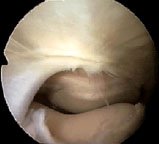

Here the arthroscope has been withdrawn above the level of the medial plica to reveal the suprapatellar plica (black arrow). You can see its position in relation to the medial plica (white arrow), which is just draping itself out of sight over the front of the femur. REMEMBER, WE ARE LOOKING FROM ABOVE, WITH THE SCOPE IS THE LARGE CAVITY ABOVE THE PATELLA. You can't see this structure from the ordinary portals!

A suprapatellar plica may stretch right across the suprapatellar pouch, dividing it into two. This is called a 'complete septum', and its presence may confuse a novice arthroscopist. It is easier for you to understand a complete septum if you see an almost complete one - what we call a 'fenestrated' plica. That means 'a plica with a window'.